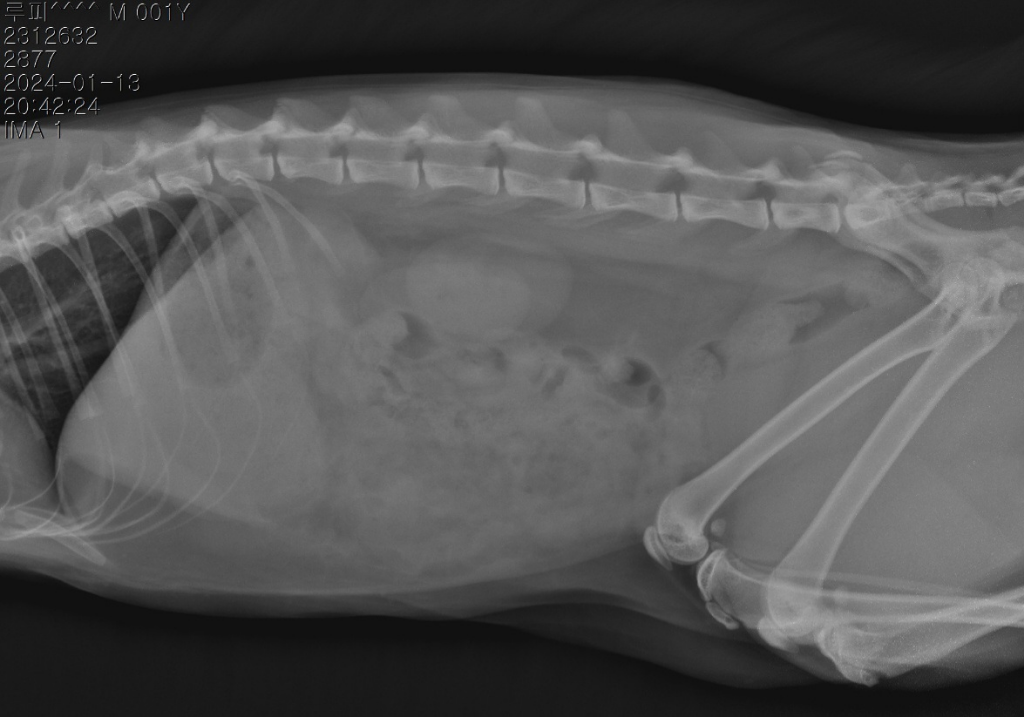

병원에서 복막염의심80% 이라고 합니다

보통 초음파까지 확인을 해봐야 알겠지만, 복수가 있으면서 복수가 짚처럼 반투명하게 노란 복수양상은 거의 고양이 전염성 복막염입니다.

급성 염증 수치는 높고 고열이 발생한 것으로 보아 감염으로 인한 질병으로 보여집니다. 초음파로 복수 확인할 수 있고, 복막염 확진을 위해서는 키트 검사나 PCR 검사를 의뢰해보시는 것이 좋겠습니다. 혈액검사 수치만으로는 알 수 없습니다.

"설사,구토는 한번도 안하고 오히려 소변만 보고 대변을 안보고 있"는것은 장폐색의 주 증상과 정 반대라고 볼 수 있습니다. 장폐색이 있으면 주로 폭발적 구토가 유발되기 때문이지요. 의심이 된다면 복부 초음파 검사를 통한 확인이 가능한 상태이니 복부 초음파 검사를 받아 보시기 바랍니다.

혈액검사 결과와 방사선 검사상 위장관의 대비도 감소 등을 볼때 심각한 수준의 장염이 또다른 원인이 될 수는 있으나 복막염 가능성이 매우 높으니 주치의와 상의하에 복막염 확진 검사를 진행하시는걸 추천합니다.